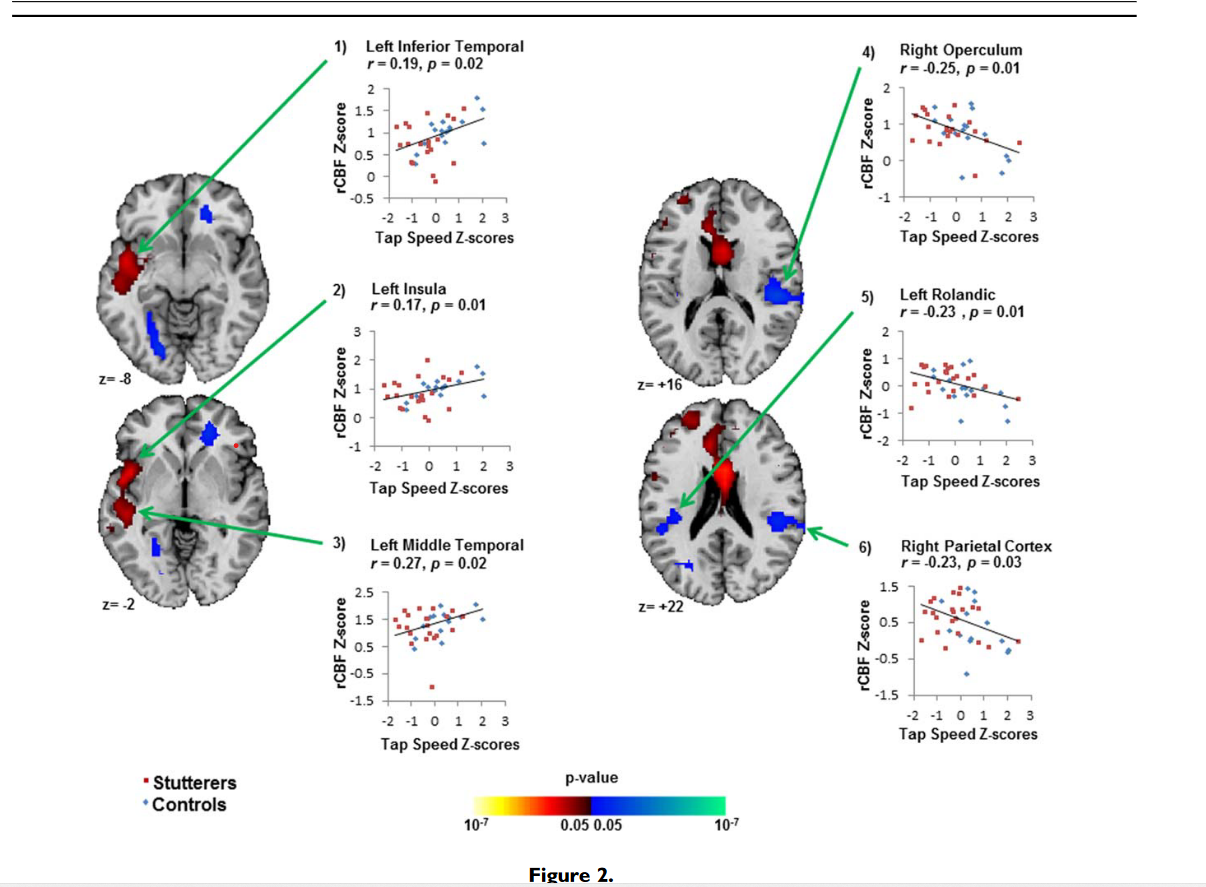

神经心理测试与rCBF:对这38名参与者的后期分析显示,rCBF与对侧感觉和运动语言区(左颞下区、左脑岛区、左颞中区)主手的手指敲击速度呈正相关,而与年龄、性别和诊断相关。研究者还检测到在双侧感觉运动区(右侧被盖区、左侧冠状叶区、右侧顶叶区)与语言区(右侧被盖区、左侧冠状叶区、右侧顶叶区)的rCBF与手指敲击速度的显著负相关(P < 0.01)(图3);但没有检测到非优势手的手指敲击速度与普渡钉板或线对半任务的分数显著相关。

这项研究首次使用灌注MRI来研究口吃者的大脑活动差异。与健康对照组相比,口吃组静息状态下双侧Broca区和额上回rCBF降低,Broca区rCBF值与口吃严重程度呈负相关,并向后延伸至语言环路的其他部分;与健康对照组相比,口吃组小脑核团和顶叶皮层的rCBF增加。在儿童分析中,所有发现都没有改变。不同年龄阶段研究结果的一致性表明,Broca区rCBF降低可能代表了一种稳定的特质脆弱性,没有这种脆弱性,口吃可能不会表现出来。灌注与口吃严重程度的负相关表明,口吃越严重,Broca区和语言环路后部的rCBF降低越大。 Broca区是用于语音生成的神经网络的关键组成部分,Broca区局部脑血流量的降低会干扰运动规划、语音和句法加工以及词汇提取,导致非流利性。这种严重程度的相关性向后延伸至弓状束的邻近组织,提示当Broca区存在的组织紊乱向后延伸至弓状束时,语言环路功能恶化,产生更严重的症状。对所有参与者的rCBF与运动表现的相关性进行的事后分析支持了对主要发现的解释。使用优势手的手指敲击速度与对侧感觉和运动语言区rCBF的正相关表明,更好的运动表现伴随着语言区更大的rCBF,口吃者语言区rCBF的减少不仅代表言语行为的计划和执行,而且更普遍地代表简单的感觉运动过程。rCBF 与语言区头侧双侧感觉运动区优势手的手指敲击速度呈负相关,这表明在感觉运动皮层中需要相对较少 rCBF 以产生相当水平的运动表现的人,这种简单运动任务的速度更快因此,它们的感觉运动皮层中的神经处理效率更高。 额斜束是连接布罗卡区和额上回的深层额叶通路,额上回负责语言的启动和自发性。该束的损伤会导致言语减慢和停顿。额上回区域 rCBF 减少可能反映斜束中的组织紊乱。神经影像学和病变研究表明,小脑核团有助于言语运动控制。在口吃组中,小脑 rCBF 的增加可能代表对Broca区和相关语言回路中存在的基于运动的不流畅的补偿反应。同样,顶叶皮层 rCBF 的增加可能代表使用高阶、多感觉整合过程来补偿口吃组的不流畅,因为功能性 MRI 研究表明顶叶皮层与参与言语产生的初级感觉运动区域有广泛的联系。感觉运动语言系统以外区域的异常 rCBF 表明网络的参与超出了负责正常语音产生的关键解剖区域。